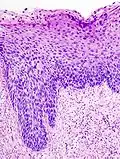

Normales zervikales Epithel. -

Die CIN wird in drei Schweregrade eingeteilt:

- CIN I: (leichte Dysplasie) geht von basal aus bis höchstens einem Drittel der Höhe des Epithels;

- CIN II: (mittelgradige Dysplasie) bis zu zwei Drittel des Epithels;

- CIN III: (hochgradige Dysplasie) durchzieht fast das gesamte Epithel (Carcinoma in situ).